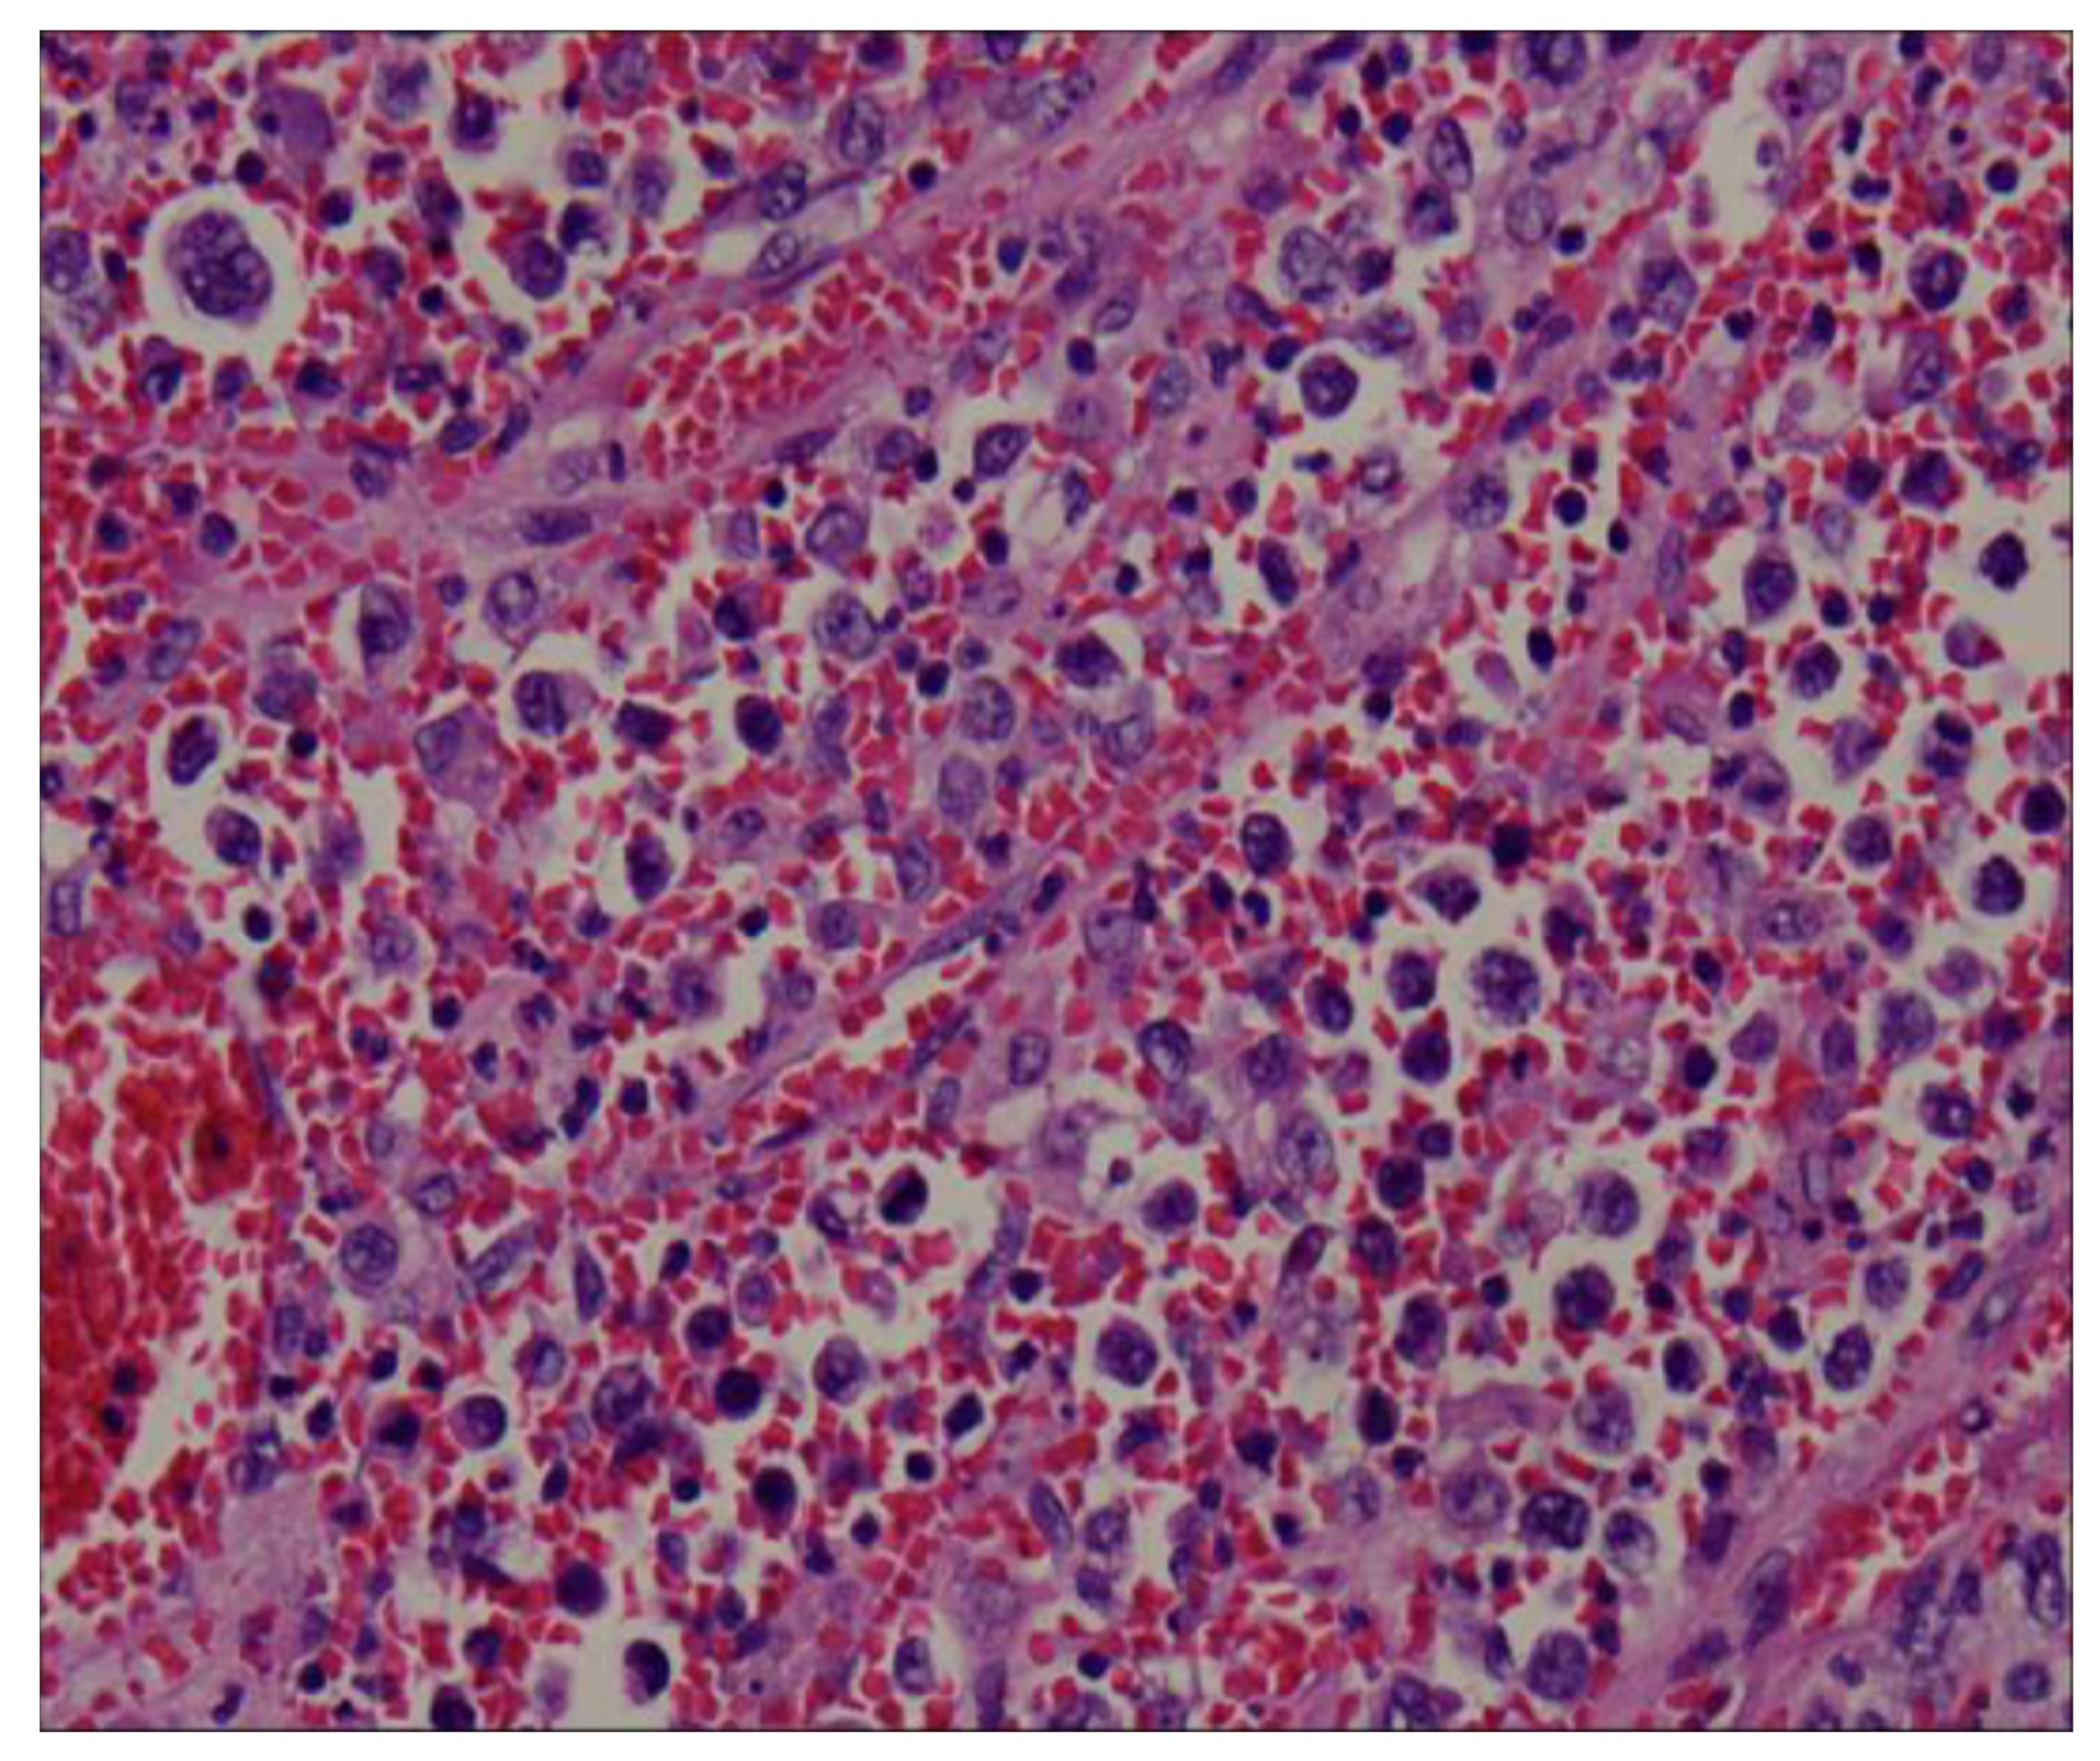

The splenectomy operation removed a large solid splenic tumor. The histology exhibited a diffuse proliferation of a monotonous population of large neoplastic lymphoid cells and extensive necrosis (Figure 4). Immunohistochemical testing revealed a positive result for CD20, CD79a, BCL6, and BCL2, and a Ki-67 index greater than 90% (Figure 5). Immunohistochemical testing was also negative for CD3 and CD10. The patient was discharged without complications 1 week later. A subsequent bone marrow examination and positron emission tomography–computed tomography scan were negative. A diagnosis of primary splenic diffuse large B-cell lymphoma was recorded. The patient received CHOP regimen chemotherapy. The patient was asymptomatic upon follow-up examination and exhibited no recurrence 6 months after chemotherapy.

Figure 4.

The histology revealed a diffuse proliferation of a monotonous population of large neoplastic lymphoid cells and extensive necrosis.

Clinical presentations of nonspecific symptoms are weight loss, weakness, fever, and left upper quadrant pain or discomfort due to an enlarged spleen. CT is the most widely used imaging modality for the assessment of lymphoma. The imaged features of splenic lymphoma are nonspecific; typical lymphoma presents as a diffusely enlarged spleen. Focal lesions appear as low-density areas in the imaging with little or no enhancement following injection of intravenous contrast medium. Ahmann classified lymphomatous involvement of the spleen into the following four categories: (1) homogeneous enlargement without masses, (2) miliary masses, (3) 2–10 cm masses, and (4) a large solitary mass [4,5,6,7]. Significant necrosis may also occur with a large tumor but extensive necrosis like the necrosis observed in our case is extremely rare.